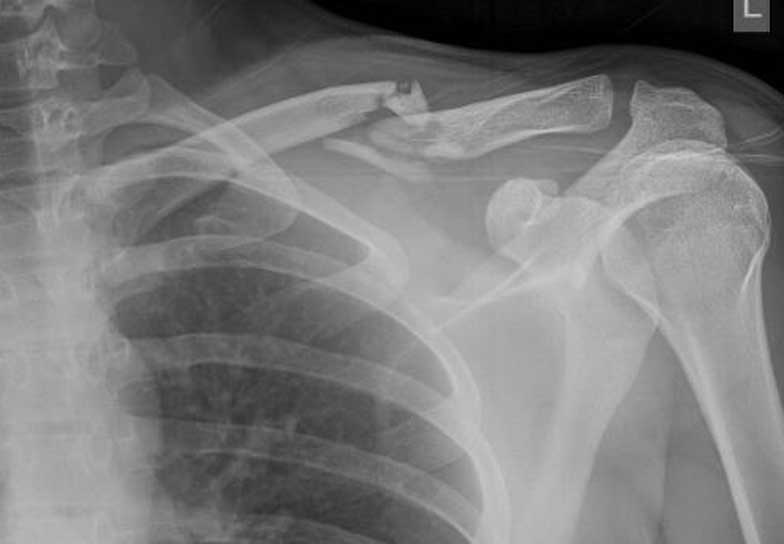

What do clavicle fractures look like on X-ray?

Below are examples of typical fractures that benefit from surgery.

A 15 year old female fell from her pushbike causing a displaced left mid-shaft clavicular fracture. Seen 5 days later, plate & screws inserted 2 days later.

Image

DIsplaced fracture before surgery